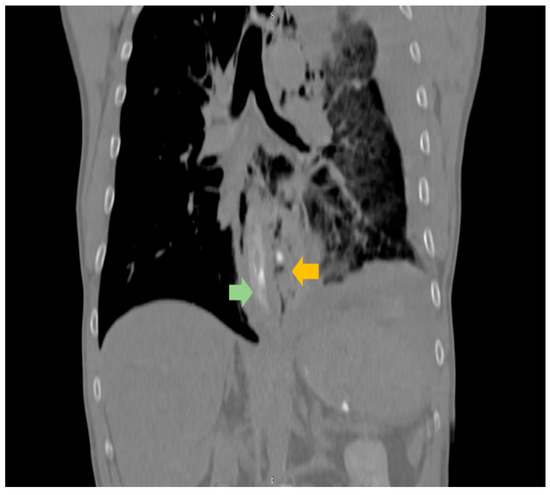

In an era where patient-reported outcomes have become more important, one of the tools that every surgeon should have in their bag is diagnostic laparoscopy. This versatile instrument can serve as a diagnostic confirmation and definitive treatment. Through a couple of trocars placed into the abdomen, a surgeon can diagnose a variety of surgical ailments, such as bowel infarction, the site of obstruction in bowel obstruction, occult hernias, and, last but not least, trauma. In addition, the oncological field is another place where it shines: intraperitoneal tumors, peritoneal carcinomatosis, and superficial liver metastases that were not identified upon imaging. Staging laparoscopy is recommended for pancreatic and gastric cancers, thus providing a potential indication for radical surgery. Laparoscopy is not only diagnostic, but after identifying the nature of the surgical disease one can perform various laparoscopic surgeries with net advantages when compared to the open approach.